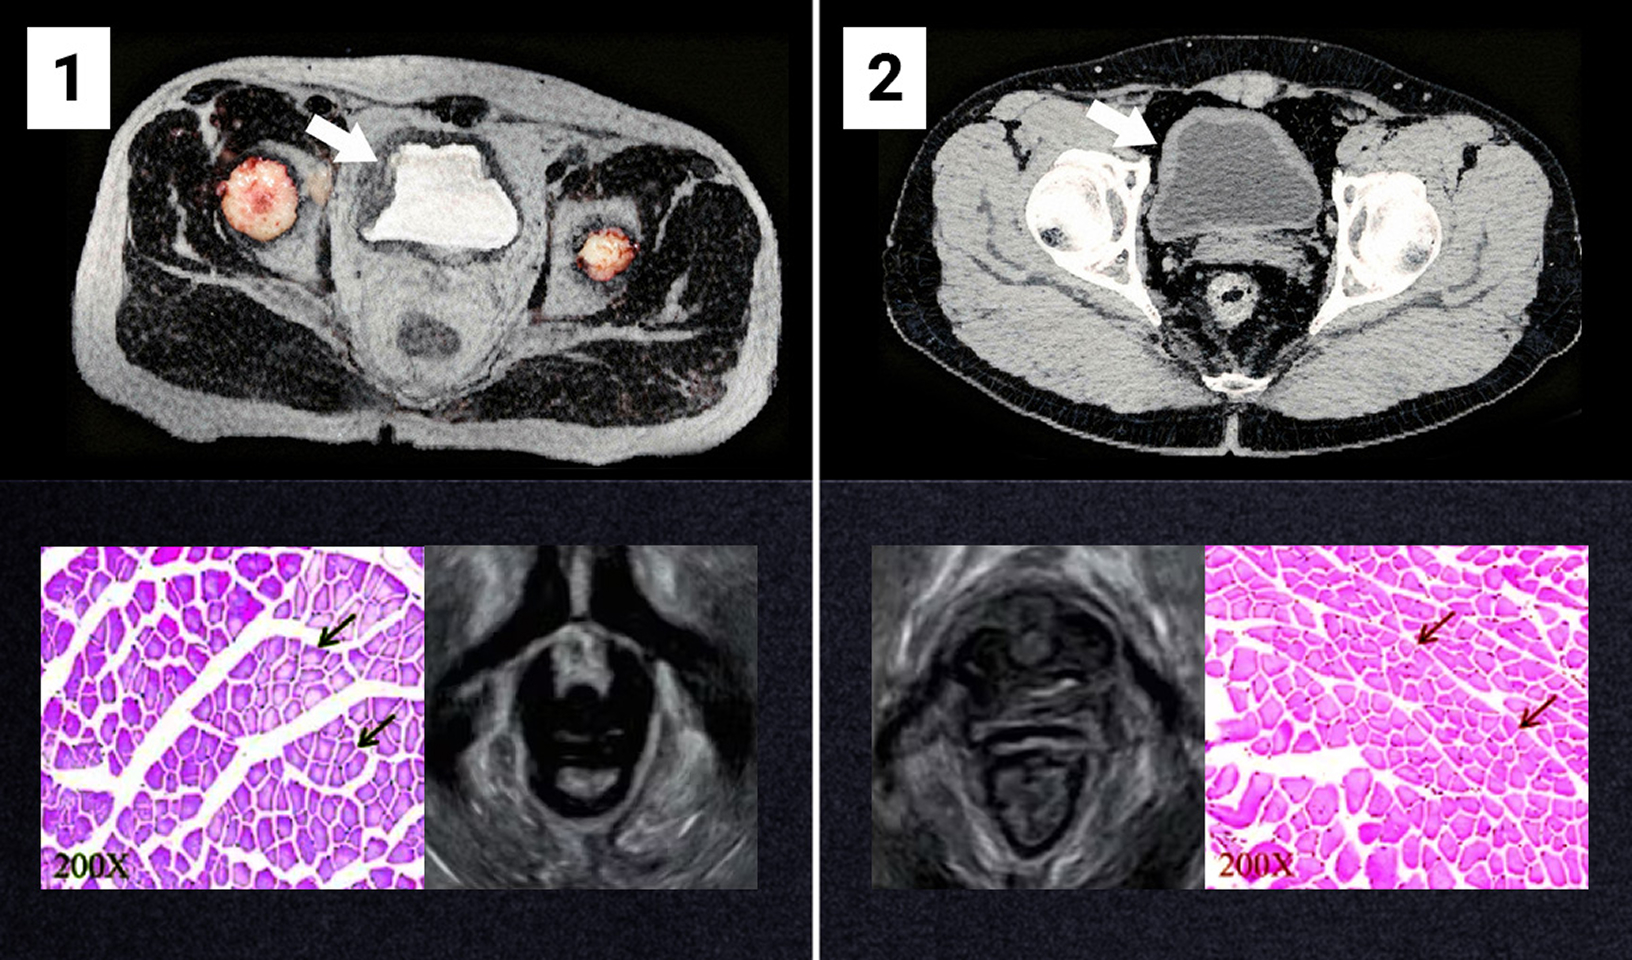

Na zdjęciu nr. 1 widoczny jest osłabiony pęcherz moczowy i niewydolne mięśnie dna miednicy. Obraz pochodzi od osoby w wieku 47 lat, cierpiącej na nietrzymanie moczu od 12 lat.

Zdjęcie nr. 2 pokazuje efekt po 4 tygodniach stosowania metody bioaktywnej (na przykładzie tej samej osoby). Mięśnie odzyskały swoje naturalne napięcie. Osoba biorąca udział w badaniu przestała mieć problemy związane z nietrzymaniem moczu.

Źródło: zasoby archiwalne zespołu prof. Hansena